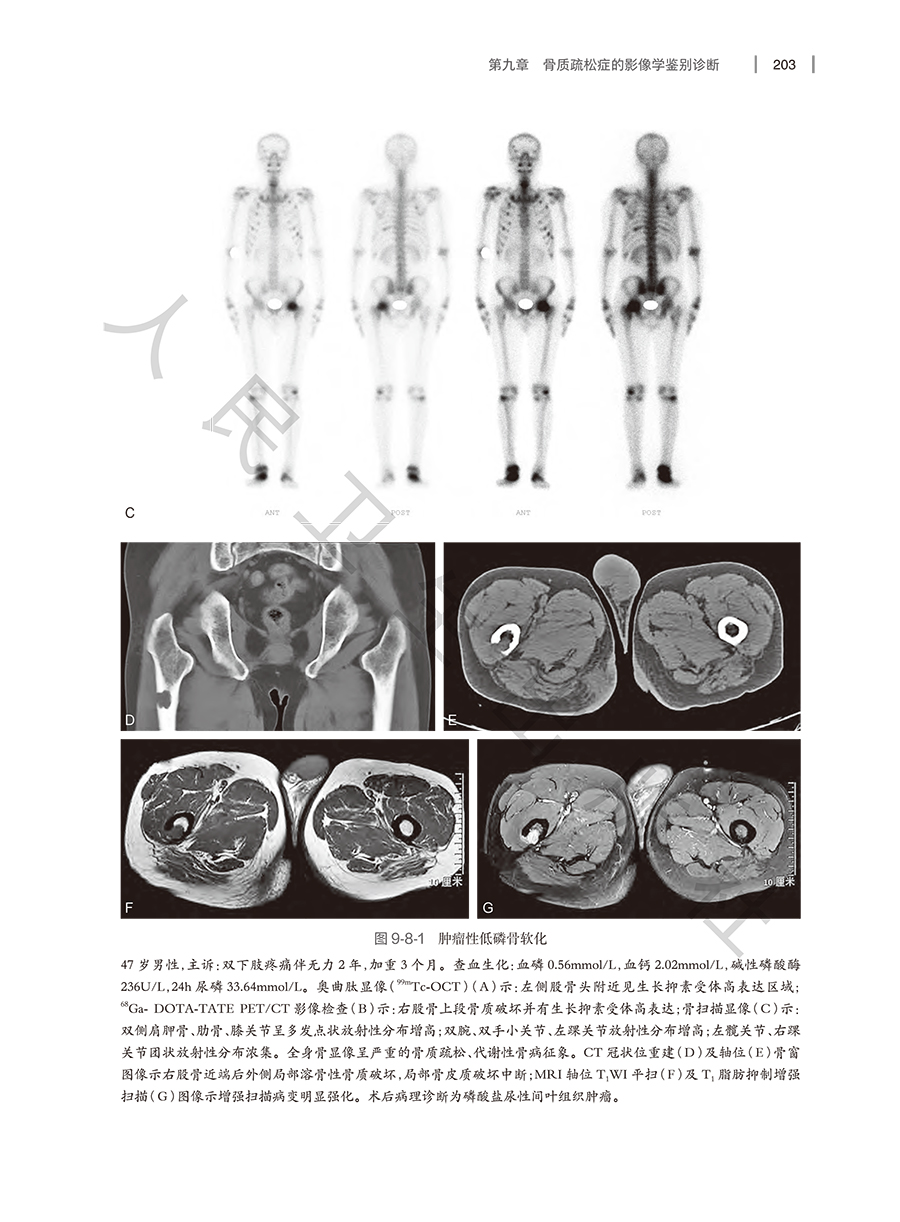

我国已进入老龄化社会,骨质疏松症严重影响老龄人口的健康,骨密度测量和影像学检查在骨质疏松症的诊断和鉴别诊断中发挥重要作用。本书从骨质疏松症的基础、临床入手,详细介绍骨质疏松症的各种影像检查技术,包括X线平片,CT,MRI和核医学在骨质疏松诊断与鉴别诊断中的作用。系统介绍各种骨密度测量方法,重点介绍双能X线吸收法(DXA)、和定量CT(QCT)骨密度测量在骨质疏松症临床诊断、评估中的应用;重点介绍定量CT影像学检查新技术在骨质疏松症诊断和评估中的应用。本书将提高影像科医生、骨科及内分泌等多学科医生对骨质疏松症的诊断和鉴别将发挥重要作用。